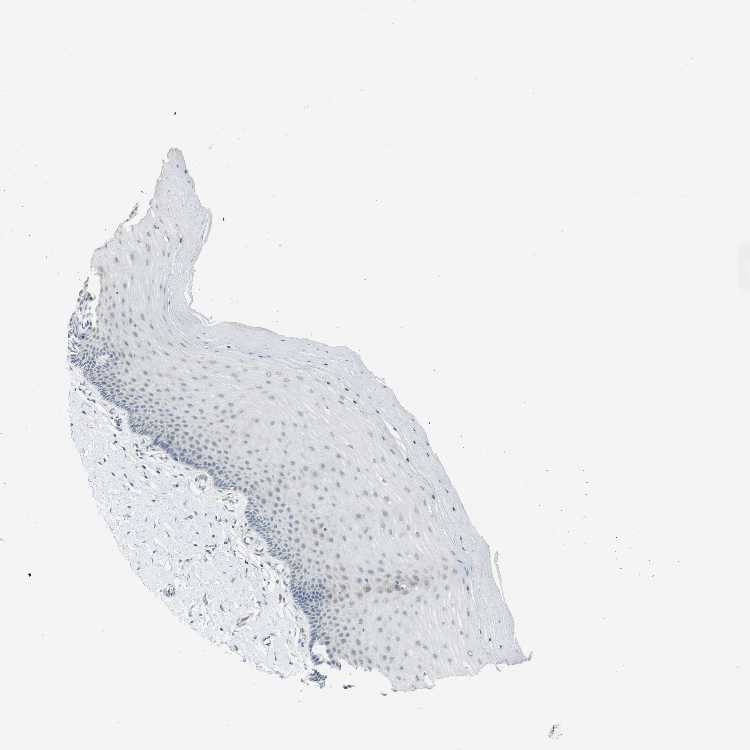

CERVIX - Antibody stainingi

Antibody staining in the annotated cell types in the current human tissue is reported as not detected, low, medium, or high, based on conventional immunohistochemistry profiling in selected tissues. This score is based on the combination of the staining intensity and fraction of stained cells.

Each image is clickable and will lead to virtual microscopy that enables deeper exploration of all samples and also displays staining intensity scores, fraction scores and subcellular localization as well as patient and tissue information for each sample.

Antibody HPA014957

Squamous epithelial cells Not detected